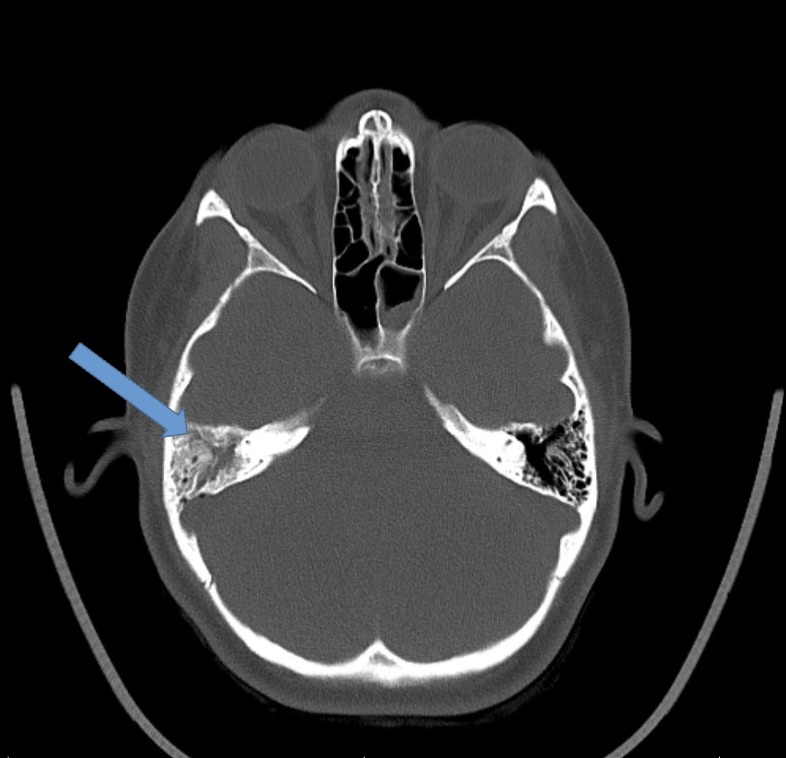

On presentation, she was afebrile and mildly tachycardic. Physical exam revealed a bulging right tympanic membrane with a purulent effusion, tenderness anterior to the sternocleidomastoid, and cheek swelling. There was no notable mastoid tenderness or neurologic deficits. Complete blood count (CBC), complete metabolic panel (CMP), C-Reactive protein (CRP), and procalcitonin were within normal limits. Blood cultures were negative. Computed tomography (CT) neck revealed right mastoiditis with dehiscence along the posterior wall of the right mastoid air cells (Figure 1) and concern for IJV thrombus. Hematology and otolaryngology were subsequently consulted. The patient was started on enoxaparin, along with meningitic-dosed vancomycin, metronidazole, and cefepime. Magnetic Resonance Imaging (MRI) and magnetic resonance venogram (MRV) of the internal auditory canals were obtained which demonstrated ipsilateral otomastoiditis with thrombosis of the right distal transverse and sigmoid sinuses (Figure 2) and proximal right IJV (Figure 3) as well as concern for cerebellar cerebritis with presence of an epidural abscess (Figure 4). The patient underwent a myringotomy with tube placement and mastoidectomy with drainage. Intraoperative findings were significant for middle ear purulence, granulation tissue in the mastoid cavity and a small sigmoid sinus defect where purulent drainage was identified. Intraoperative cultures were positive for Streptococcus pneumoniae resistant to clindamycin, erythromycin, penicillin, tetracycline, and trimethoprim-sulfamethoxazole. Ophthalmology was consulted to evaluate for papilledema, where grade one optic disc edema was noted. After post-operative recovery, she was discharged with a PICC line for 42 days of intravenous vancomycin and ceftriaxone, oral metronidazole, along with 6 months of enoxaparin for anticoagulation.